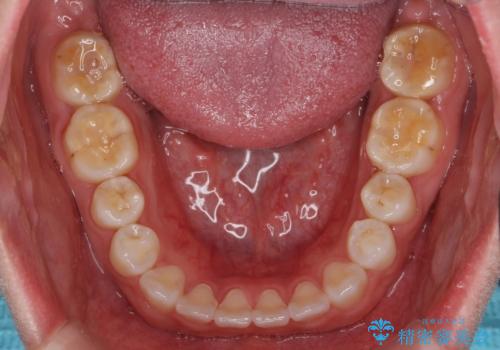

インビザライン 気になるすきっ歯の改善

- 上下顎前歯部の空隙が気になるので治したいと当院にいらっしゃった方の症例です。

非抜歯、インビザラインによる矯正治療により歯と歯の隙間および前歯の上下の隙間を閉じ切りました。